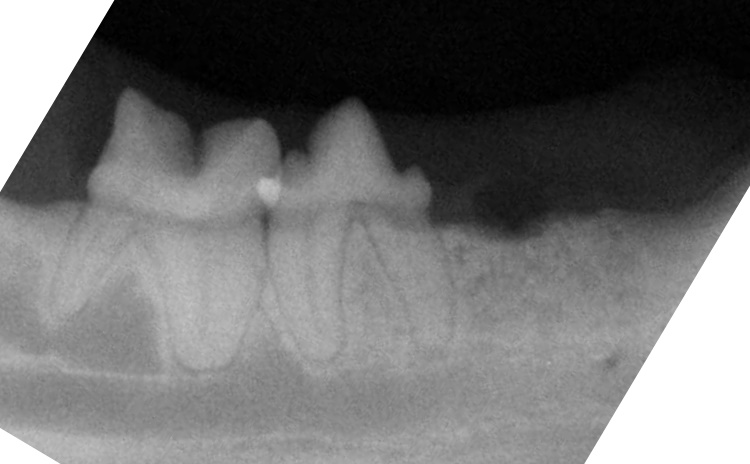

Another cat with lower third premolar tooth affected by tooth resorption.

This tooth is severely affected by resorptions. This is a Type 2lesion (exhibiting root replacement by bone with no clearly observable periodontal ligament space).

This tooth was treated with complete extraction.

This tooth was treated with crown amputation.